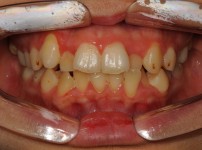

9

BEFORE

AFTER

클릭 해주세요.

앞니 벌어짐

치아교정